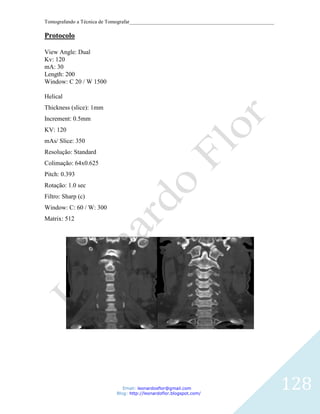

Protocolo

Helical

Thickness (slice): 1mm

Increment: 0.5mm

KV: 120

mAs: 150

Resolução: High

Colimação: 64x0.625

Pitch: 0.923

Rotação: 0.75

Filtro: Y- Detail (YD)

Window: C: 300 / W: 3000

Matrix: 512